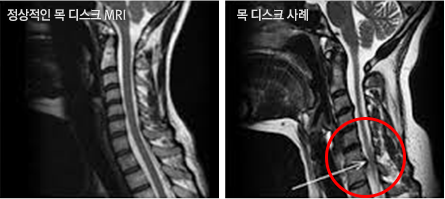

목 디스크의 사례